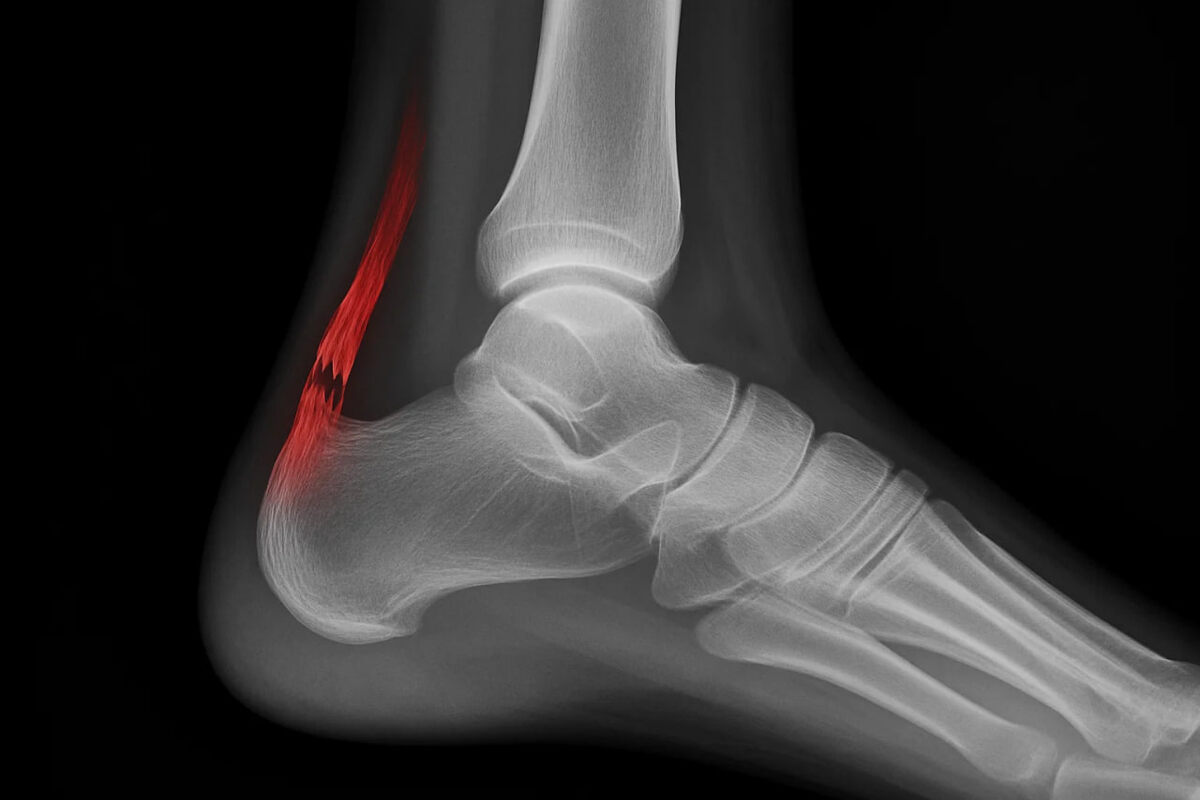

🔢Ахиллово сухожилие

Связывает икроножную мышцу с пяточной костью. С возрастом оно становится хрупким, а разрыв часто означает длительную реабилитацию.